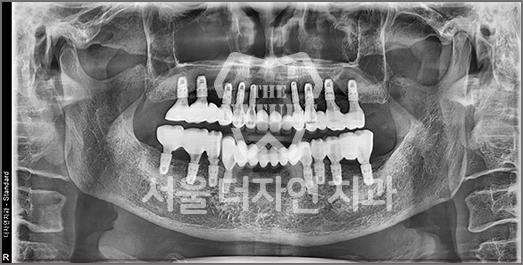

Full-Mouth Implant Restoration

Implant treatment for comprehensive full-arch restoration

This implant option is chosen to fully restore dental function. When missing teeth have been left untreated for an extended period,

the alveolar bone volume in both the maxilla and mandible is often insufficient. Therefore, a precise surgical plan must be established

with careful consideration of each patient's overall health condition.

• AFTER: 2023.02.23

• BEFORE: 2022.12.15